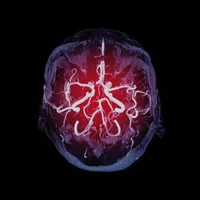

• Examens neurologiques pour évaluer la fonction nerveuse.

• Imagerie médicale, comme l'IRM ou le scanner, pour rechercher des anomalies structurelles.